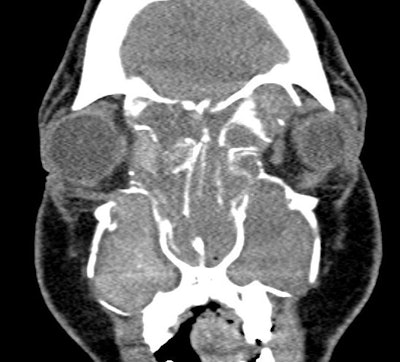

Figure 1. CT demonstrating the unilateral expansile disease process, which ultimately was determined as AFRS.

AFRS is a subtype of chronic rhinosinusitis with nasal polyps (CRSwNP) that accounts for approximately 5%-10% of chronic rhinosinusitis cases. It is characterized by a robust type 2 inflammatory profile, hypersensitivity to fungal antigens, and unique molecular pathways.1,2 Compared with other subtypes of CRSwNP, patients with AFRS tend to present younger and are more likely to present with unilateral findings. Further, AFRS is primarily seen in geographic regions with warm, humid climates.1,2,3

Clinically, AFRS often presents with substantial polyp burden and dense eosinophilic mucin with a “peanut butter” consistency (Figure 2A and B). CT can be helpful demonstrating classic findings of heterogeneous sinus opacification with areas of hyperattenuation and metallic-type “double densities” on soft tissue window (Figure 3).4 The disease process characteristically causes expansile changes to the paranasal sinuses, which can lead to expansion and erosion of the bony orbit, skull base, and facial skeleton (Figure 3).